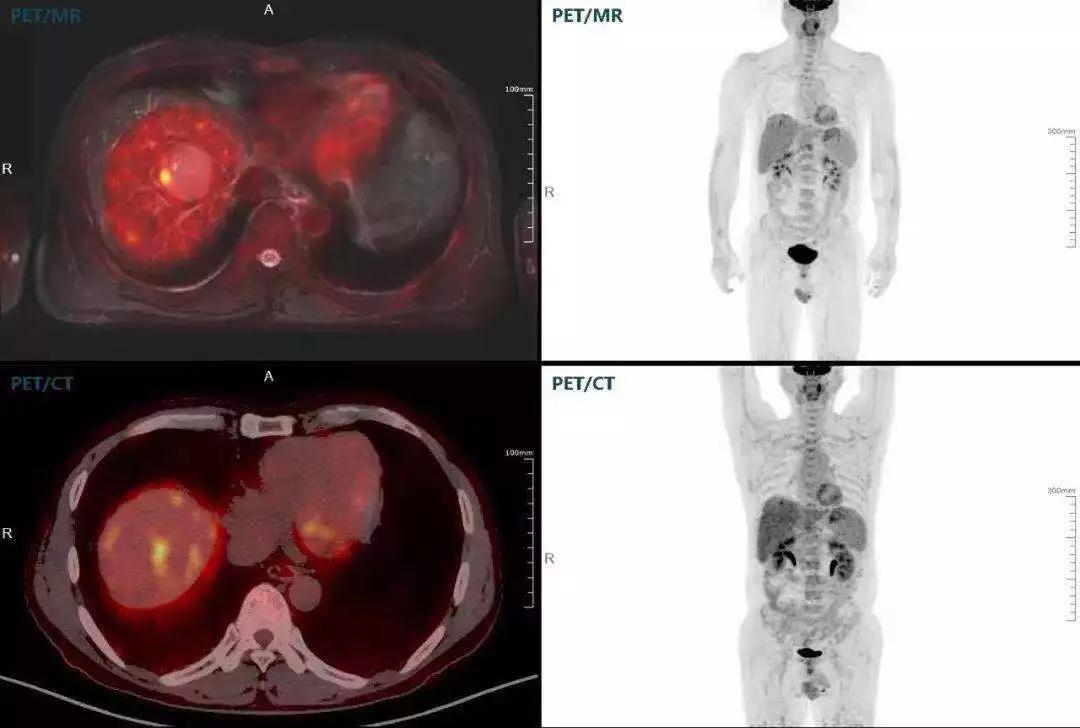

肝癌

聯(lián)影“時空一體”超清TOF PET/MR搭載的壓縮感知技術,能夠同時實現16期成像,精準捕獲肝臟動態(tài)影像的每一瞬間,同時兼顧早期與晚期等全部期相的完整病灶信息,實時、全方位鎖定病灶。同時,基于其2.8mm超高分辨率,能夠精細呈現腫瘤邊界信息,捕捉局部微小病灶與遠端轉移灶,助力醫(yī)生精準診斷。

(對于同一例肝臟惡性腫瘤,PET-CT與PET/MR成像對比。可以看到,聯(lián)影PET/MR圖像對腫瘤邊界和FDG高濃聚區(qū)域清晰顯示。)